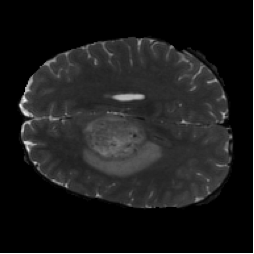

Diffusion with U-shape (Figure 5, PDF page 8)

Diffusion input MRI slice.

Input MRI

DICE 69.44% · Best qualitative and quantitative segmentation quality.